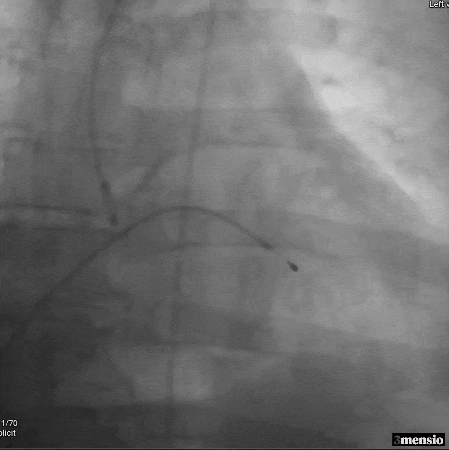

冠脉造影

图片